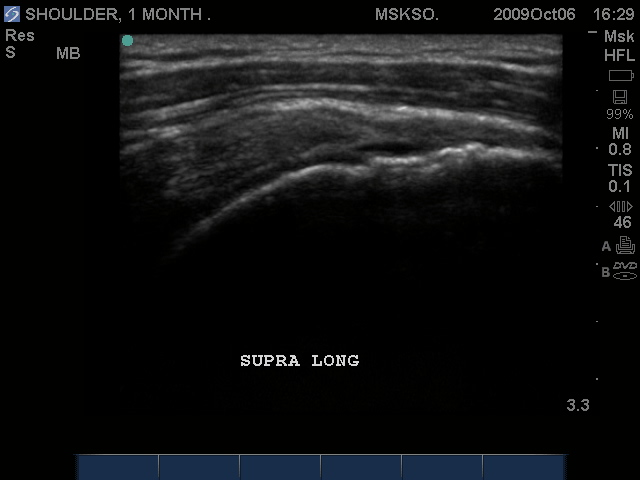

Compression of the tear site may reveal a more normal cuff appearance, in this case, the flattening of the normally convex appearing bursal surface would indicate that there is volume loss at this level.

Transverse and Long axis images should always be taken to demonstrate 2 imaging planes 90 degrees from each other.